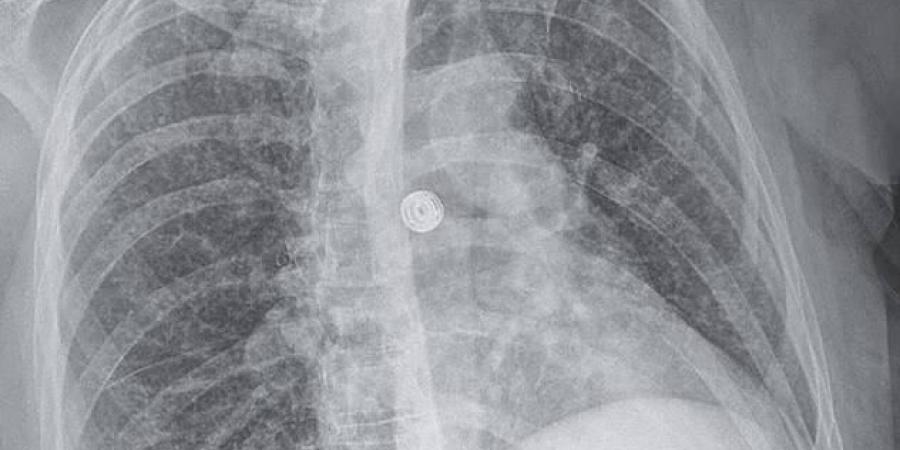

أظهرت الفحوص الشعاعية وجود عقيدات صغيرة منتشرة في الرئتين، إلى جانب آفات في الكبد والغدد اللمفاوية والبنكرياس والدماغ. وبعد 9 أسابيع، أكدت التحاليل المخبرية إصابتها ببكتيريا المتفطرة السلية المسببة لمرض السل، في شكل نادر يعرف بالسل المنتشر الذي يصيب أعضاء متعددة من الجسم.